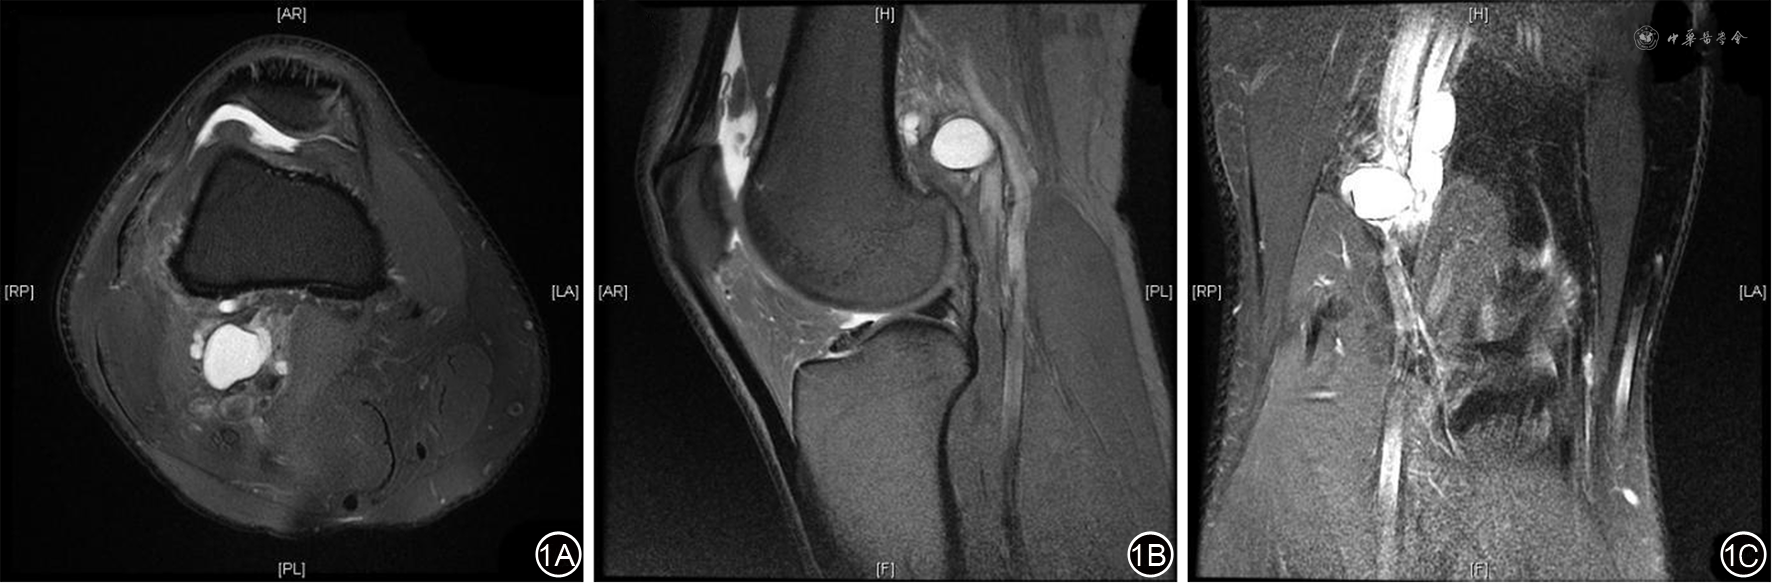

患者男,49岁,因右下肢间歇性跛行2月余入院。该患者2个月前无明显诱因,行走或跑步运动后出现右小腿疼痛麻木,休息后可缓解,症状反复出现,现跛行距离约200 m,无静息痛。入院查体:右下肢股动脉搏动正常,腘、足背和胫后动脉无法触及搏动。入院前超声检查:右侧股浅、腘、胫后和腓动脉流速减低,频谱形态改变,三相波消失。CT血管三维成像示:右侧腘动脉P1段重度狭窄,腘动脉后外侧受压。膝关节MRI示:腘动脉后外侧见一类圆形异常信号影,边界清晰,T2WI高信号,大小1.7 cm×2.5 cm,长约3.1 cm(图1)。初步诊断:腘动脉陷迫综合征(popliteal artery entrapment syndrome,PAES)、腱鞘囊肿(ganglion cyst,GC)。硬膜外麻醉下行右侧腘动脉解压+囊肿切除术。术中见腘动脉被股二头肌肌腱长头远端内侧面的肌腹内囊肿压迫,囊壁表面光滑,质韧,内容物为淡黄色胶冻样。囊肿切除后行术中超声示腘动脉流速、三相波恢复正常,结束手术。术后病理符合腱鞘囊肿的病理特征。术后4个月随访,右侧股、腘、足背和胫后动脉搏动正常,下肢血管超声检查未见明显异常。